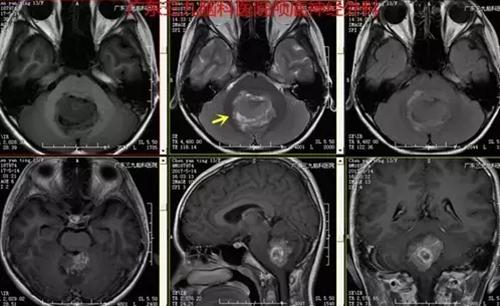

图2:术前磁共振提示肿瘤位于四脑室底-小脑蚓部、大小约3.8*2.9*3.5cm,不均匀强

本例患者为13岁11月儿童,因头痛伴呕吐入院,颅内压增高症状明显,入院时MR提示病变位于四脑室底-小脑蚓部。本例患者手术过程短,术后恢复快,未有明确并发症,术后复查头颅MR提示肿瘤全切。